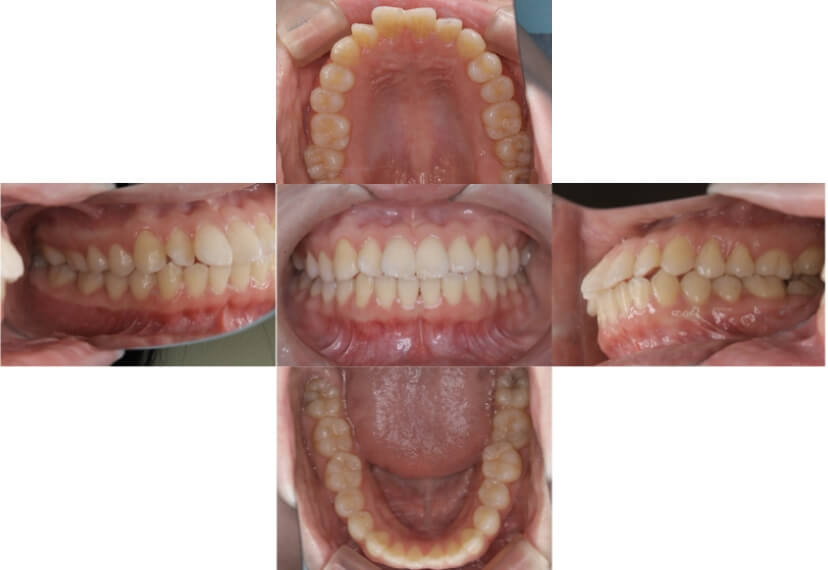

BEFORE

AFTER

上下顎叢生、上顎前突(出っ歯、上下の前歯のガタガタ)のケースです。

装置はラビアル(上下表側)で、上顎の小臼歯を2本抜歯を行っています。抜歯したスペースを使って、上の前歯の後方移動と叢生(ガタガタ)と出っ歯の改善を行っています。下は歯と歯の間にIPR(隣接面削合)を行い、スペースを確保し、叢生の改善を行っています。

主訴 前歯のガタガタと出っ歯が気になる。

年齢・性別 47歳 女性

お住まいの地域 神奈川県川崎市

治療方針 抜歯スペースおよびIPRを利用して上前歯の叢生(ガタガタ)の改善

抜歯部位 上顎左右第一小臼歯

使用装置 ラビアル(上下表側)、顎間ゴム

治療期間 2年0か月

治療回数 15回

リテーナー クリアリテーナー